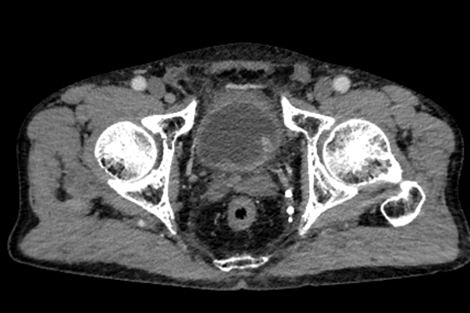

多年来,贵州航天医院各科室紧跟医学前沿,不断强技术、补短板,大力开展新技术、新项目,完成了许多高精尖、高难度、本地区“首例”的技术,填补了医院医疗技术空白,满足了群众日益增长的医疗需求。 本期,我们将为大家带来泌尿外科特色技术——腹腔镜膀胱癌根治术+原位新膀胱术,保留患者自然排尿功能。 案例分享 患者(60岁)在当地医院检查发现膀胱多发肿瘤,在行膀胱肿瘤电切术后,病理提示:高级别尿路上皮癌,该院医生建议患者进行根治性膀胱切除,但切除后肚子上将存在永久造瘘并需佩戴腹壁尿袋,尿液不能自己控制,随时会从肚子流出。 患者拒绝接受挂尿袋的方式,在辗转多个医院咨询后,得知贵州航天医院泌尿外科具有切除膀胱后肚子上不用佩戴尿袋的技术,于是前来我院就诊。泌尿外科腔镜组组长李凯教授带领团队经过反复研究病史及阅片,充分考虑患者需求并征得患者及家属同意后,决定为患者实施腹腔镜根治性膀胱切除术+原位回肠新膀胱术。 CT示膀胱内多发肿瘤 经过6个多小时紧张的手术,顺利切除膀胱并取长约40cm的肠管重新整合成新膀胱,再与输尿管、尿道吻合后原位代替病变的膀胱。切除的组织经过病理检测,提示:恶性上皮肿瘤,符合膀胱高级别浸润性尿路上皮癌,侵及深肌层。 术后3天,患者可以正常排尿;1周后顺利出院;1月后拔出双侧单J管及尿管,患者反馈小便顺畅,无尿失禁等不良情况出现;3月后患者进行尿流率检测,自主排尿通畅。 术后腹壁伤口愈合良好 患者术后3月新膀胱影像 术后3月,患者行尿流率检测 自主排尿通畅 腹腔镜膀胱癌根治术+原位新膀胱术代表了现代泌尿外科技术的最高水平,它不仅为膀胱癌患者提供了根治肿瘤的机会,还通过微创技术和功能重建,帮助患者重获高质量的生活。贵州航天医院泌尿外科李凯教授团队结合患者实际情况对该技术进行了改良,全手工缝合新膀胱,确保患者排尿正常且避免了结石等并发症的出现,已完成多例手术,在遵义地区处于一流水平,为遵义地区患者健康保驾护航。 咨询信息:贵州航天医院便民服务电话 什么是腹腔镜膀胱癌根治术+ 原位新膀胱术 膀胱癌是泌尿系统常见的恶性肿瘤之一,传统的手术方式虽然有效,但创伤大、恢复慢,患者需终生佩戴腹壁尿袋,生活不便且影响社交,给患者带来了极大的身体和心理负担。随着医学技术的不断进步,腹腔镜膀胱癌根治术+原位新膀胱术成为治疗膀胱癌的先进选择,以其精准、微创、恢复快的优势,为患者带来了新的选择和希望。 腹腔镜膀胱癌根治术+原位 新膀胱术原理 腹腔镜膀胱癌根治术是一种微创手术,通过腹腔镜技术,医生可以在高清影像的引导下,精准切除病变的膀胱及周围可能受侵的组织。与传统开腹手术相比,腹腔镜手术切口小、出血少、术后疼痛轻,患者恢复更快。 原位新膀胱术则是在切除膀胱后,利用患者自身的肠道组织(通常为回肠)构建一个新的膀胱,并将其与尿道连接,使患者能够通过正常途径排尿,极大提高了术后生活质量。相比传统的尿流改道术(如回肠代膀胱术),原位新膀胱术更符合生理结构,患者无需佩戴尿袋,生活质量显著提升。 腹腔镜膀胱癌根治术+原位 新膀胱术优势 (一)微创精准,减少创伤 腹腔镜手术通过几个小切口完成操作,避免了传统开腹手术的大切口,减少了术中出血和组织损伤,术后疼痛轻,恢复快。 (二)原位新膀胱,恢复自然排尿功能 原位新膀胱术重建了患者的排尿功能,术后患者可以通过尿道正常排尿,避免了佩戴尿袋的不便和心理压力。 (三)术后并发症少,恢复快 由于手术创伤小,术后感染、肠梗阻等并发症的发生率显著降低,患者住院时间短,能够更快回归正常生活。 (四)提高生活质量 原位新膀胱术不仅保留了患者的排尿功能,还减少了术后对生活的影响,患者可以更好地融入社会和工作。 术后康复与护理 术后患者需遵循医生的指导,逐步恢复饮食和活动。早期可能需要进行膀胱功能训练,以适应新膀胱的排尿功能,定期复查和随访是确保术后长期效果的关键。 友情提醒: 发现无痛性肉眼血尿,需警惕泌尿系肿瘤,尤其是发病率较高的膀胱癌,须尽早就诊。 贵州航天医院泌尿外科专家团队 石 英 泌尿外科主 任 学科带头人 主任医师 中国医师协会泌尿外科分会感染协作组委员,奥林巴斯泌尿系软镜西南区专家组成员,西南地区第一批输尿管软镜专家组成员,贵州省医学会泌尿外科分会委员,贵州省性学会理事,贵州省性学会常务委员,贵州省泌尿外科专业医疗质量控制中心专家委员会委员。 从事泌尿外科专业近30年,熟练掌握泌尿系各类疾病的诊治,具有丰富的临床经验,擅长泌尿系结石、腹膜后肿瘤及泌尿系肿瘤的手术治疗,对泌尿系感染、泌尿系结核、尿源性脓毒血症的救治有独到的见解及抢救经验,在贵州省率先引入输尿管软镜技术,同时在男科领域,对男性阳痿、早泄及前列腺疾病有很深的研究。 李 凯 泌 尿 外 科 副 主 任 医 师 贵州航天医院肿瘤腔镜组带头人,擅长肾癌根治术、输尿管癌根治术、膀胱及前列腺癌根治术、腹腔镜输尿管狭窄切除吻合术、输尿管切开取石术等手术,在遵义市率先开展泌尿系结核后膀胱挛缩全腹腔镜下膀胱扩大术。 贵州省医学会泌尿外科分会青年委员,遵义市医学会男科分会常务委员,遵义市医学会泌尿外科分会常务委员。 李国成 泌 尿 外 科 副 主 任 医 师 中国人体健康科技促进会男科学专业委员会委员,贵州省性学会泌尿外科分会委员,贵州省医学会男科学分会委员,遵义市医学会男科学分会副主任委员兼秘书长,遵义市医学会泌尿外科分会常务委员,贵州航天医院男科带头人。 从事泌尿外科及男科工作10余年,曾多次在上海交通大学附属第一人民医院,中国中医科学院西苑医院进修学习男科;擅长性功能障碍的诊治,男性整形手术,前列腺增生激光手术,显微手术等。 贵州航天医院泌尿外科简介 • ✦ 基本情况 ✦ • 贵州航天医院泌尿外科创建于1968年,经过几代人的努力,微创与内镜手术占比达90%以上。是贵州省临床重点专科建设单位、北京清华长庚医院李建新教授团队诊疗及会诊中心、北京医学会尿路修复与重建诊疗及会诊中心、上海公济泌尿外科集团遵义中心、上海援黔专家李铮教授男科工作室、贵州省泌尿外科质量控制专家委员单位,科室亚专业框架已完善。 • ✦ 专科特色技术 ✦ • (一)泌尿系结石内镜碎石技术 泌尿系结石微创治疗领域方面是贵州省首家引进科医人钬激光碎石技术科室,在遵义地区率先掌握输尿管硬镜、软性镜,经皮肾镜钬激光碎石技术。目前是北京清华长庚医院泌尿外科“手把手”经皮肾镜碎石技术培训基地、贵州省输尿管软镜培训基地。 1.负压吸引可弯曲软镜鞘电子软镜碎石术 2.标准与超微通道相结合的经皮肾镜碎石取石术 (二)微创腹腔镜技术 泌尿外科腹腔镜技术师承于浙江省人民医院、北大、北京解放军总医院。目前采用经腹、经后腹双入路法的腹腔镜技术完成肾部分切除、肾切除、肾输尿管全长切除、肾盂输尿管成形、输尿管狭窄吻合、膀胱翻瓣等手术。在遵义地区率先掌握腹腔镜下膀胱癌根治术、腹腔镜下前列腺癌根治术。 (三)男科、盆底技术临床应用 遵义地区男科分会主委单位,是贵州省首家引进尿动力学检查并取得了全国资质认证科室,也是贵州省首家进行RigiScan检查的单位。在遵义地区率先掌握显微取精子技术以及显微镜下治疗精索静脉曲张、显微镜下输精管吻合、输精管附睾吻合技术。率先采用前列腺激光剜除术治疗前列腺增生症。在陆军军医大学西南医院泌尿外科主任沈文浩教授指导下,完成遵义市首例神经源性膀胱骶神经调节刺激器置入术。 • ✦ 诊疗范围 ✦ • 诊疗范围(除外肾移植、癌栓):泌尿系结石、泌尿系肿瘤、肾上腺疾病、肾积水、前列腺增生、男性生殖器功能障碍(精索静脉曲张、生殖道感染、输精管梗阻等)、盆底功能障碍性疾病(膀胱脱垂、排尿功能异常、尿失禁)、泌尿生殖系畸形。 泌尿外科拥有独立门诊治疗室、日间手术室、尿动力学检查室、精液分析检查室、男性勃起功能检查及治疗室、ESWL治疗室、结石分析检查室。